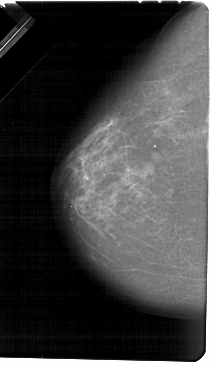

A_1328_1.LEFT_MLO

LEFT_MLO LINES 5491 PIXELS_PER_LINE 3361 BITS_PER_PIXEL 12 RESOLUTION 43.5 NON_OVERLAY